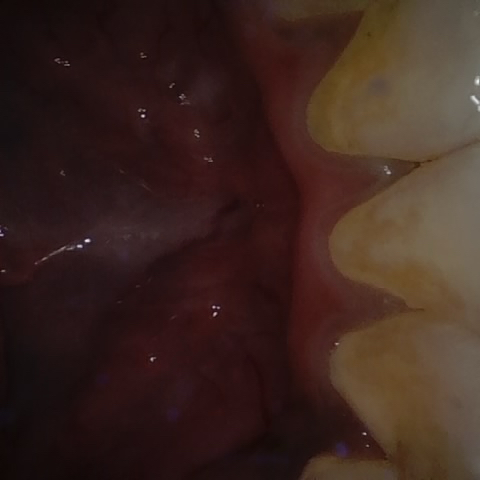

Annotated as "Good"